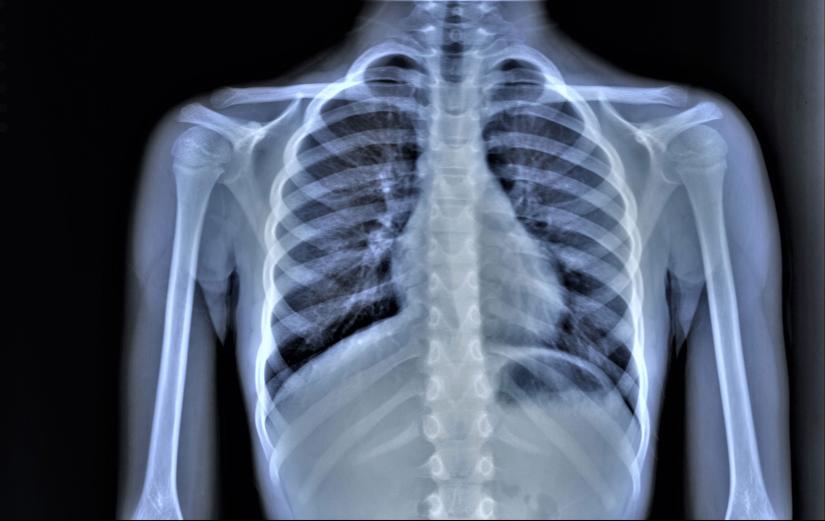

They will often also undergo an X-ray, usually to confirm which parts of the lung are involved.

Healthy lungs look “empty” on an X-ray, because they are filled with air. But pneumonia fills the lungs with fluid.

This means it’s usually very easy to see where pneumonia is affecting them, because the infection shows up as solid white mass on the scan.